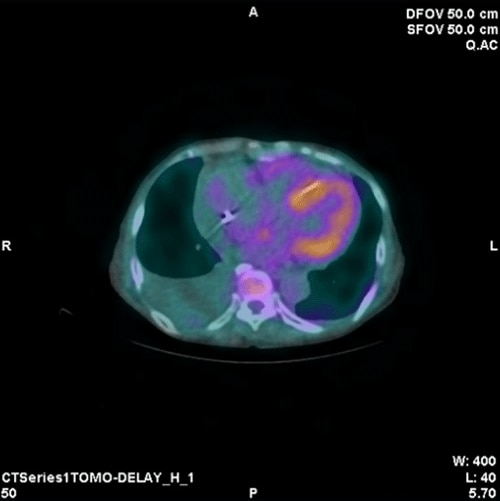

ピロリン酸シンチグラフィ検査では通常SPOT像における定量値、定性画像の評価により心アミロイドーシスの鑑別を行いますが、それに加えてSPECT/CTのFusion画像を作成することによって心筋へのピロリン酸の集積をより分かりやすく表示することが可能です。

ピロリン酸シンチグラフィ CT画像とのFusion